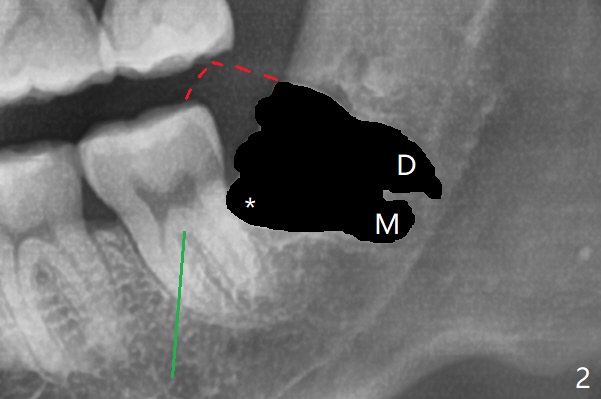

A 27-year-old man requests extraction of the tooth #17. Immediately following 4Q SRP (Fig.1), a midbuccal incision is made (Fig.2 green line) to reduce the chance of graft exposure in case of wound dehiscence because of nearly horizontal impaction of #17. The crown of the latter may be slight mesial to the distal surface of the tooth #18. In fact this is the case after flaps are raised. Since the socket is expected to be large, the graft will be placed immediately distal to the tooth #18 (Fig.2 *), while collagen plug (Fig.3,4 C) will be placed in the root portion of the socket (Fig.2 M, D (mesial and distal)) and in the gingival area (red dashed line to prevent graft material escape). Return to Plug Cement Xin Wei, DDS, PhD, MS 1st edition 06/22/2020, last revision 06/25/2020